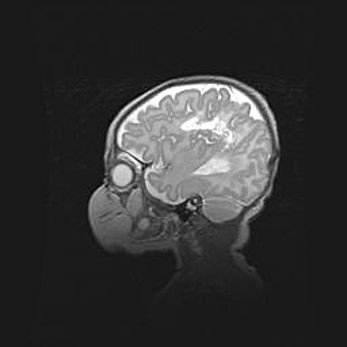

Неполная лизэнцефалия (пахигирия). Открытая гидроцефалия.

Возраст: 17 дней

Вес: 3110 г

Пол: мужской

Окружность головы: 33,5 см

Срок гестации: 35-36 недель

Лизэнцефалия—недоразвитие корковой пластинки и мозговых извилин в результате нарушения миграции нейронов коры. Поверхность мозговых полушарий гладкая. Микроскопически выявляется отсутствие нормальных слоев коры и скопление групп нейронов в подкорковом белом веществе.

Пахигирия—уменьшение числа вторичных извилин. В пораженном полушарии нервные клетки образуют толстый недифференцированный слой с неправильно расположенными нервными волокнами и группами гетеротопных клеток. Нервные клетки незрелые. Белое вещество истончено. При этом нередко аномально развит корково-спинномозговой путь.